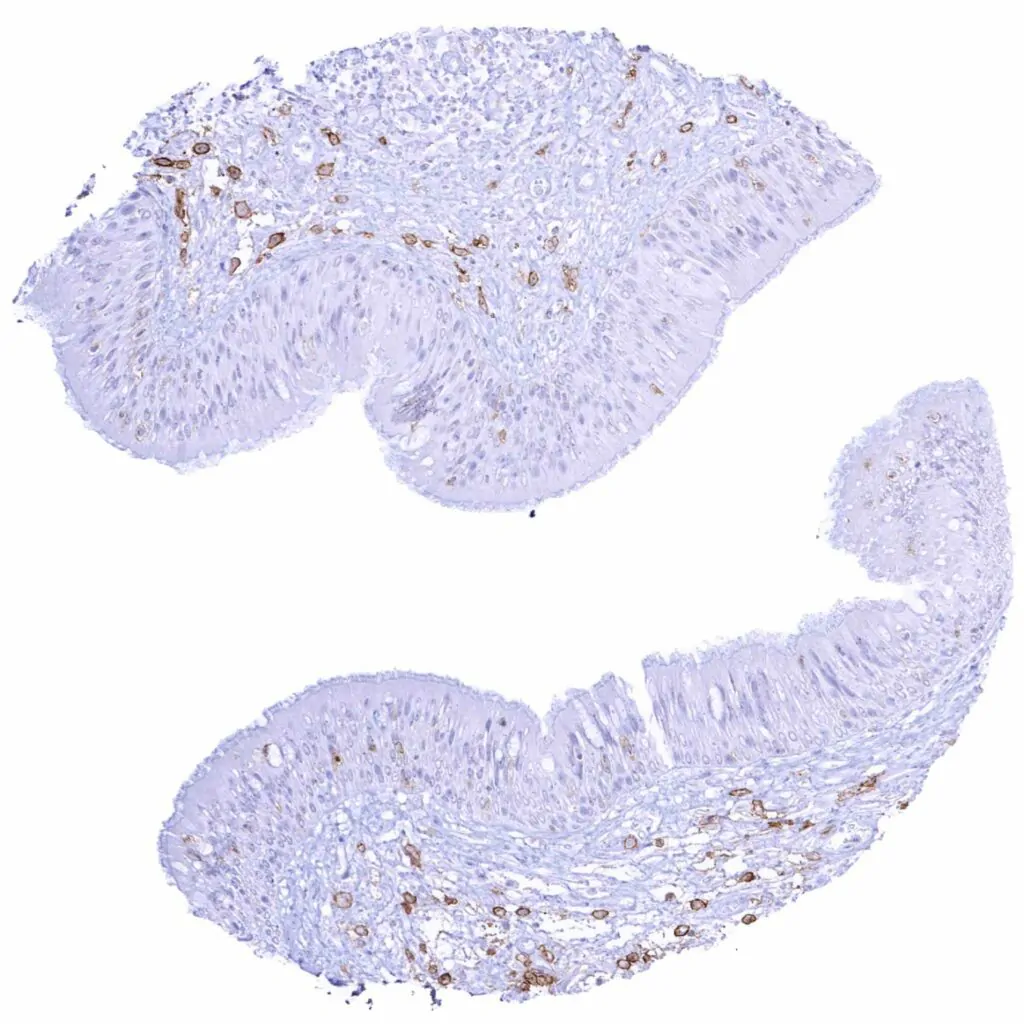

Appendix, mucosa – Strong CD38 staining of a subset of inflammatory cells

Appendix, mucosa

Appendix, muscular wall